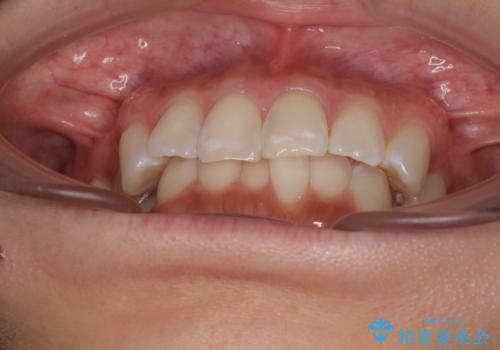

なかなか舌の突出癖が改善できず、上下前歯が非接触となる期間が長く続きました。

アンカースクリューの活用と、舌のトレーニングを何度も指導し、出っ歯になることなく無事に治療を終えることができました。